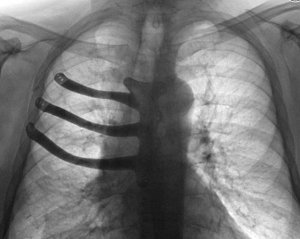

71-річному Пітеру Меггзу через рак довелося видалити половину грудної кістки і три ребра. Їх вдалося відновити завдяки 3D-принтеру. Про це повідомляє ABMU Health Board.

Раніше в подібних випадках хірурги відливали протез з медичного цементу під час операції, але технологія 3D-друку дозволила виготовити імплант з титанового сплаву і скоротити час операції на дві години. При виготовленні протеза використовувалася комп'ютерна томографія грудної клітини пацієнта. Це один із перших випадків друку подібних протезів.

Медики розповіли, що операція тривала 8 годин і пройшла успішно, що дозволить використовувати цю технологію у майбутньому.